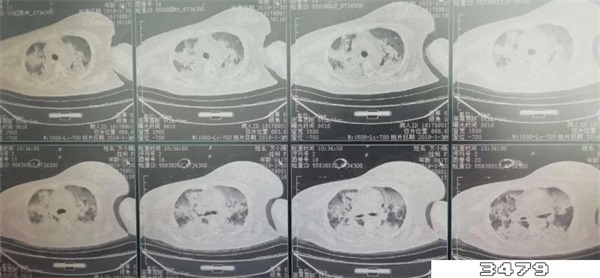

新冠白肺是不可逆的,白肺患者的肺组织会发生几乎不可逆的肺纤维化、肺功能损伤。白肺是不可以也不会自愈的,如果不对白肺进行及时干预治疗的话,可能会导致人体无法正常进行呼吸和气血交换氧气,严重的话会危及生命。

同济大学附属上海市肺科医院呼吸监护室副主任医师张黎表示:重症的白肺患者,死亡率超过40%以上。虽然有部分患者可以治愈,但是肺部难以恢复到原来的健康状态,绝大多数患者会留下肺部纤维化的后遗症。

白肺最大的问题就是会导致氧气不能通过肺泡腔进入气血屏障,然后进行气血交换。人体长时间得不到氧气就会对器官造成损伤,甚至会因为无法呼吸而死亡。若出现呼吸困难,呼吸次数大于30/分钟,氧饱和度低于90%,建议及时就医。